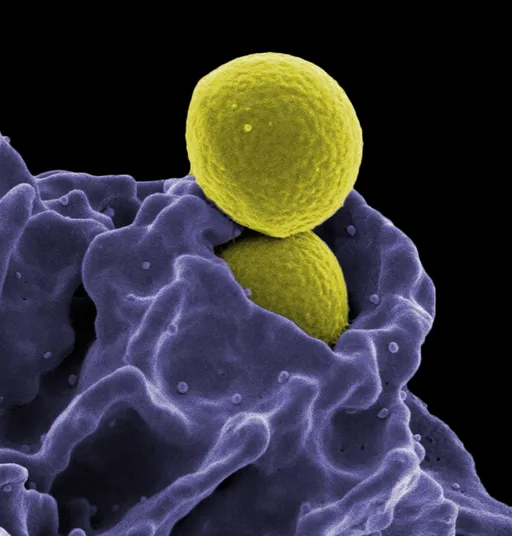

Cancer